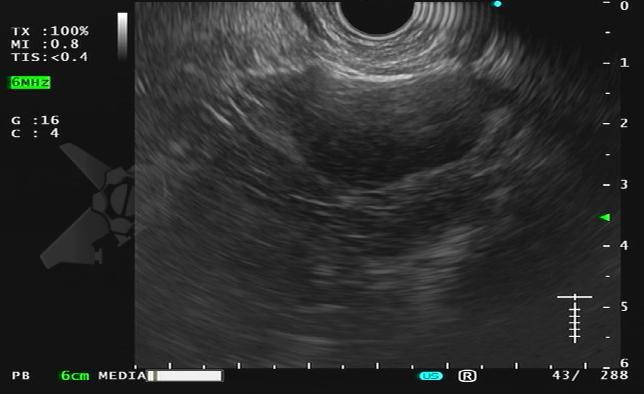

Durante exame de ecoendoscopia, a imagem a seguir foi identificada na adrenal esquerda:

Diante deste achado incidental, qual seria a sua conduta?

- Discussão multidisciplinar

- Punção ecoguiada com FNA

- Punção ecoguiada com FNB